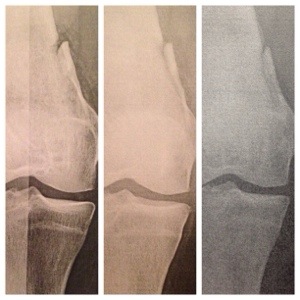

I know I already posted the pic of my x-ray from last week, but I didn’t realize just how much things had progressed until yesterday when my PT and I compared it with some of the old x-rays I had on my phone.

The above pic shows the x-ray right out of surgery on the left, one 6 weeks later in the middle, and the most recent one on the right taken at 6 months. It’s easy to see the healing that has taken place when you put them side by side, especially with the piece of bone they took off to get at the tumor on the inside.